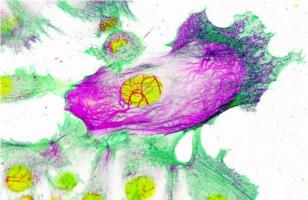

Actualité publiée le 22/04/2021TROUBLES CÉRÉBRAUX : Des nanoparticules qui ciblent et soignent le cerveau

Actualité publiée le 11/01/2021